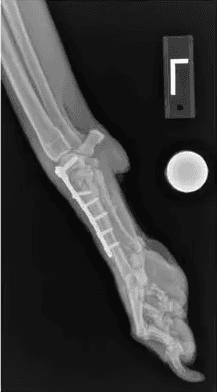

Pantarsal Arthrodesis

This procedure is a complete fusion of the ankle joint where all joint surfaces are removed of cartilage, bone graft filled into these spaces, then the ankle held in a standing angle with a bone plate/screws. Pantarsal Arthrodesis eliminates the need for the Achilles tendon.

It is a more aggressive procedure undertaken when tendon reconstruction has failed or if tendon reconstruction is not desired due to the potential for failure or long recovery time. Initially, the stabilization is protected with a splinted bandage or cast for 6-8 weeks. Exercise restrictions continue for a total of 12-14 weeks to allow complete fusion before return to normal activity.

Pancarpal/Pantarsal Arthrodesis

A complete arthrodesis involves fusion of the entire joint, eliminating all range of motion. A complete arthrodesis is necessary when the tibiotarsal or radiocarpal joints are affected. The cartilage is removed between all joints within the wrist or ankle then filled with bone graft. A specialized bone plate and screws are used to stabilize the bones until they fuse completely.